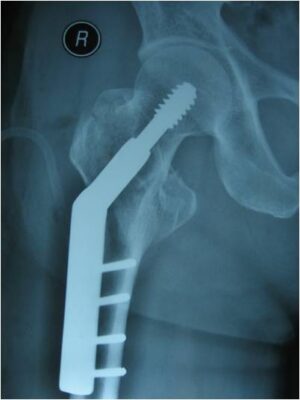

- Phim X-quang luôn được chỉ định để xác định loại gãy. Thường phim thẳng và nghiêng xương chậu và khớp háng là đủ để đánh giá khả năng gãy xương. Xoay trong hoặc xoay ngoài chân cũng có thể làm tăng độ nhạy của các hình chụp X quang này. Dựa vào X quang, cugnx có thể xác định độ vững của xương gãy, tiên liệu phương pháp can thiệp phẫu thuật.

- Trong trường hợp gãy xương hông ngoài bao khớp, điều trị tiêu chuẩn là phẫu thuật bằng mổ hở và cố định trong.

- Ở bệnh nhân gãy liên mấu chuyển vững, khuyến cáo sử dụng nẹp vít trượt (DHS) hoặc đinh nội tuỷ (M)

- Bệnh nhân với gãy liên mấu chuyển không vững nên được điều trị với đinh nội tuỷ (M)